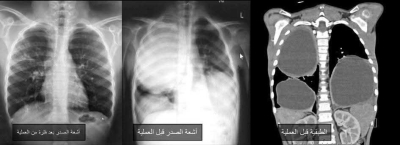

الوقائع الإخباري: تمكن فريق جراحة الأطفال في مستشفى الجامعة الأردنية من علاج حالة نادرة لطفل يبلغ 9 سنوات، كان يعاني من "أكياس كلابية" ضخمة في كلتا الرئتين، عبر تدخل جراحي دقيق باستخدام المنظار الصدري، في إنجاز طبي يعد من الحالات القليلة المسجلة عالميًا.

وأوضح بيان المستشفى، الصادر اليوم الأحد، أن ندرة الحالة تكمن في أن "الأكياس الكلابية" تصيب الكبد غالبًا وقد تمتد إلى الرئتين، بينما تعد إصابة الرئتين بشكل متعدد وضخم في الجهتين حالة نادرة جدًا، وقد اكتشفت دون أعراض واضحة من قبل استشاري أمراض الصدرية للأطفال الدكتورة إيناس الزيادنة وفريقها الطبي.

ونظراً لتعقيد الحالة وصعوبتها التخديرية والجراحية، تولى فريق التخدير بقيادة استشاري تخدير الأطفال الدكتور عمر عبابنة تقديم رعاية متقدمة، مكنت من إجراء عمليتين جراحيتين كبيرتين ومتتاليتين بأمان، فيما أجرى فريق جراحة الأطفال برئاسة استشاري المنظار الدكتور رائد الطاهر العمليتين بنجاح كامل دون مضاعفات، باستخدام المنظار الصدري بدلاً من فتح الصدر التقليدي.

كما ساهم استخدام المنظار والثقوب الجراحية الصغيرة في تسريع تعافي الطفل بعد العملية الأولى للرئة اليمنى، ما أتاح إجراء العملية الثانية للرئة اليسرى بعد أسبوعين فقط بنفس التقنية، وتابع الفريق الطبي حالة الطفل لأشهر، مؤكداً عودته لممارسة حياته الطبيعية دون أي مضاعفات.